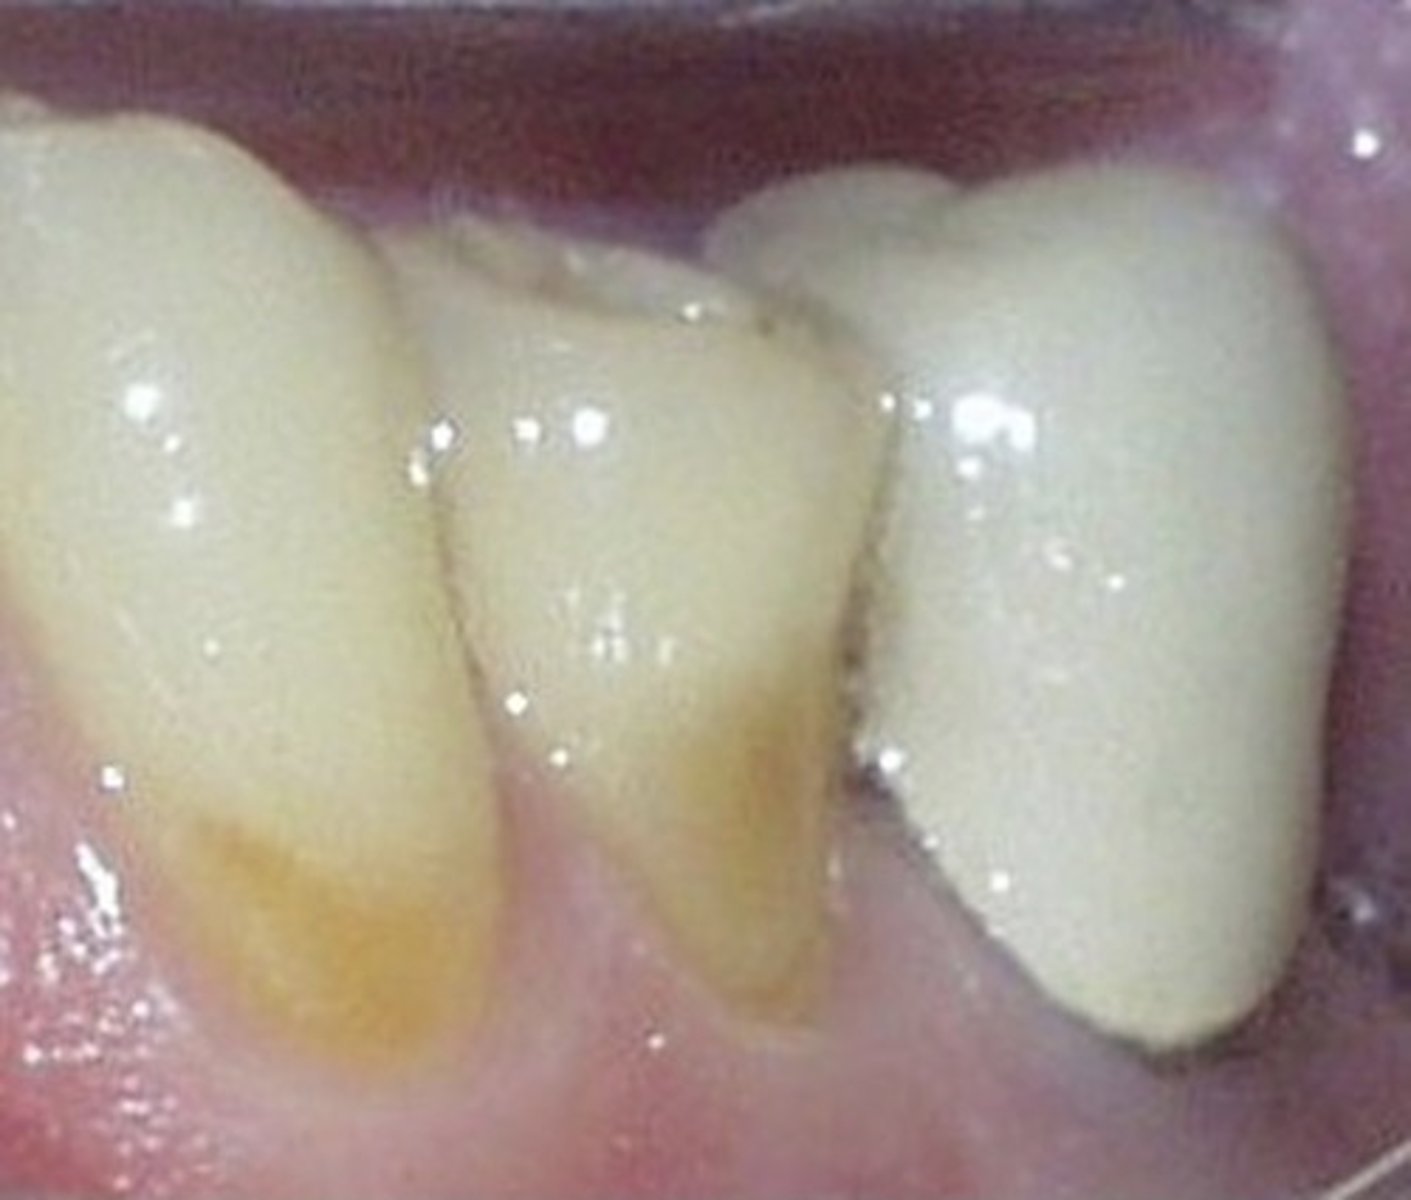

arrested

carious lesion that has not progressed, hard surface with a dark color

calculus